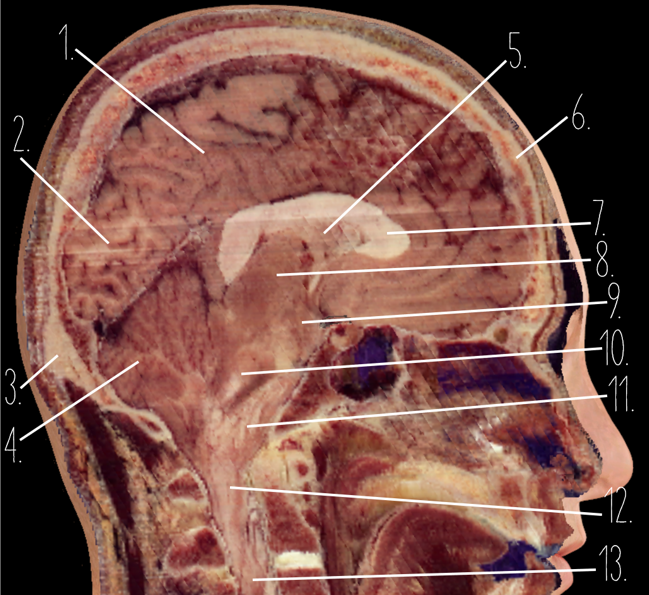

Brain Cross Sectional

127 Terms

1

Frontal Bone

2

Frontal Lobe

3?

Falx Cerebri

4?

Gray Matter

5?

White Matter

6?

Sulcus

7?

Gyrus

8?

Fissure

1?

Parietal Lobe

2?

Cerebellum

3?

Occipital Bone

4?

Cerebellum

5?

Lateral Ventricle

6?

Frontal Bone

7?

Corpus Callosum

8?

Thalamus

9?

Hypothalamus

10?

Midbrain

11?

Pons

12?

Medulla Oblongata

13?

Spinal Cord